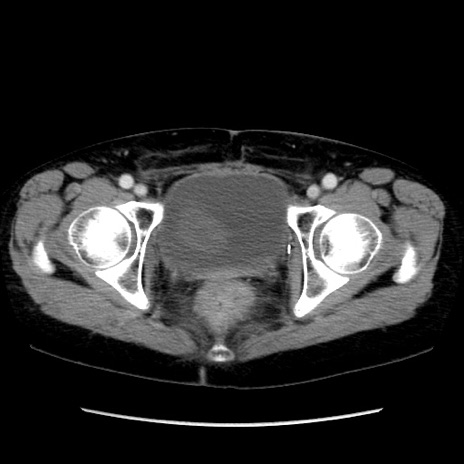

症例32(横断像)

【症例】40歳代 女性

【主訴】上腹部痛、嘔気・嘔吐

【現病歴】約9時間前頃から急に上腹部痛、嘔気、嘔吐が出現。改善しないため救急要請。

【既往歴】子宮頚癌(広汎子宮全摘術、放射線療法)、腸閉塞

【身体所見】腹部:平坦、軟、腸雑音亢進、上腹部を中心に腹部全体に圧痛あり。

【データ】WBC 8400、CRP 0.03